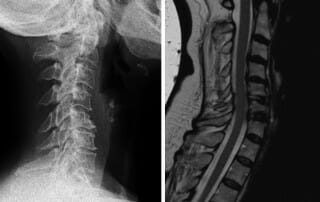

Prof. Linhardt Fallbeispiel: Fehlstellungen und Spinalstenosen der HWS

Operative Möglichkeiten bei Fehlstellungen und Spinalstenosen der HWS anhand eines Fallbeispiels von Prof. Linhardt im OZA München Wirbelsäulenzentrum: Das seitliche Röntgen und MRT-Bild einer 58-jährigen Patientin mit jahrelangen Schmerzen [...]